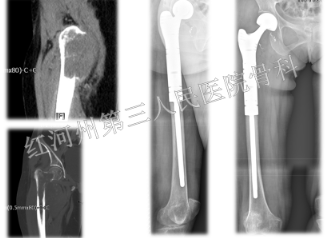

还有一位60岁女性患者,乳腺癌并右侧股骨转子间转移,合并病理性骨折,疼痛评分7分,经过综合评估,选择组配式髋关节置换,术后快速恢复下床运动,疼痛评分1分。

再如另外一位患者,右侧股骨恶性肿瘤,病例提示低分化肉瘤。术前合并病理性骨折,疼痛评分7分,患者长期卧床,不能站立。经过右侧股骨瘤段切除,组配式髋关节置换,术后髋关节功能快速恢复,疼痛评分1分。